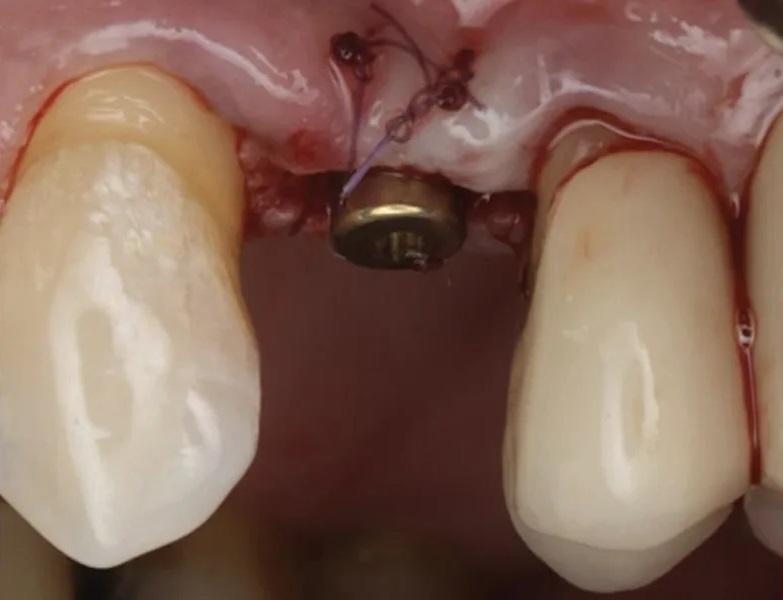

Раскрытие имплантата: Через шесть месяцев после установки имплантата были выполнены оценка мягких тканей и рентгенография (Фото 17). Была проведена местная инфильтрационная анестезия препаратом Septocaine, выполнен гребневой разрез для обнажения ранее установленного имплантата. Была установлена формировательная головка (Фото 18). ПА рентгеновский снимок подтвердил краевое прилегание абатмента к имплантату (Фото 19). Участок был ушит швом ПТФЭ, и пациенту были даны инструкции по гигиене полости рта и послеоперационному уходу. Контрольный осмотр проведен через 2 недели после раскрытия имплантата, мягкие ткани выглядели здоровыми (Фото 20 и Фото 21).

Фото 17. Окклюзионный вид здоровых мягких тканей и ширины гребня через 6 месяцев после установки имплантата.

Фото 18. Вестибулярный вид непосредственно после раскрытия имплантата, установки абатмента и коррекции вестибулярной мягкой ткани.